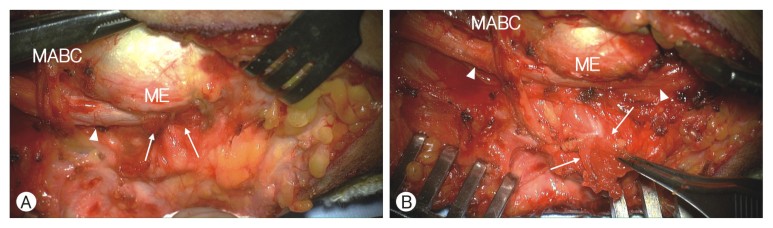

여기서 화살표는 aconeuse pitrochlearis이고 화살표는 척골신경입니다.환자는 수술 후 2개월까지 감각은 개선되었지만 운동 기능은 개선되지 않았습니다.왼손 잡는 능력이 떨어졌는데요.수술 6개월째부터 악력이 회복되기 시작하여 12개월 후에 완전히 회복되었다고 합니다.

Ultra sound Diagnosis of Double Crush Syndrome of the Ulnar Nerveby the Anconeus EPitrochlearis and a Ganglion 척추신경에 의해 신경포착이 발생하는 것은 팔꿈치와 손목에서 가능합니다.이 논문은 doublecrushsyndrome이라고 해서 팔꿈치와 손목 모두에서 포착이 발생한 경우입니다.오른쪽 그림의 초음파를 보면 AE(도르래상주근)에 의해 압박되는 팔꿈치의 척골신경과(cubital tunnel) ganglion에 의해 압박되는 손목의 척골신경을 볼 수 있습니다. (guyontunnel) 척골신경은 주관(팔꿈치)과 가이온터널(손목)로 동시에 압박될 수 있는 이를 doublecrushsyndrome이라는 이 논문의 환자는 오른쪽 손가락의 저린 감각력 부족으로 내원했습니다.(팔꿈치 신경을 누르면 감각 이상이나 운동 이상이 발생합니다) 수술을 통해 팔꿈치의 (anconeuse pitrochlearis) 활차상의 낮근을 감압하고 손목에서 2cm 정도의 ganglion을 제거하였습니다.이 환자는 수술 후 증상이 호전돼 1년간 증상이 없었습니다.